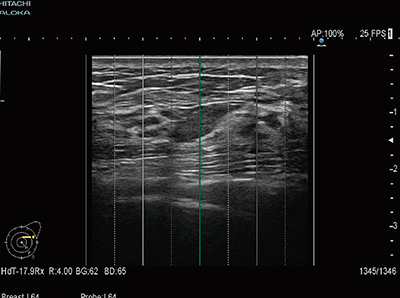

プローブ(L64)の長軸方向につけられた,5mm 間隔の目盛に対応するラインをBモード画像上に表示します(図2)。アシストラインは,体表に印をつけるマーキングの補助として使用できます。

図2 アシストライン表示